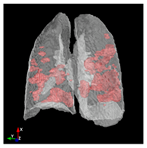

In Table 6, a comparison of the ground truth and prediction results of each model is presented in 2D, along with the 3D projection of each model. The visual analysis of the predictions provides additional insights into the performance of each model. The visualizations demonstrate that Attention UNet captures the intricate details of the lung construction more accurately, resulting in more precise segmentation of the infected areas compared to other models.

Table 6.

Comparison of ground truth and model prediction results using UNet, LinkNet, Attention UNet, UNet 3+, and TransUNet.

Attention UNet stands out due to its sophisticated attention mechanisms that allow it to focus on relevant regions and features within the lung structures. This characteristic enhances its ability to capture intricate details specific to COVID-19-affected lungs. The attention mechanisms contribute to Attention UNet’s impressive IoU score of 85.36% and dice score of 91.49%, showcasing its potential to provide accurate and finely detailed segmentations. The results suggest that its trait of dynamically assigning different weights to regions, based on their contextual importance, is instrumental in achieving precise and meaningful segmentations in complex medical images.